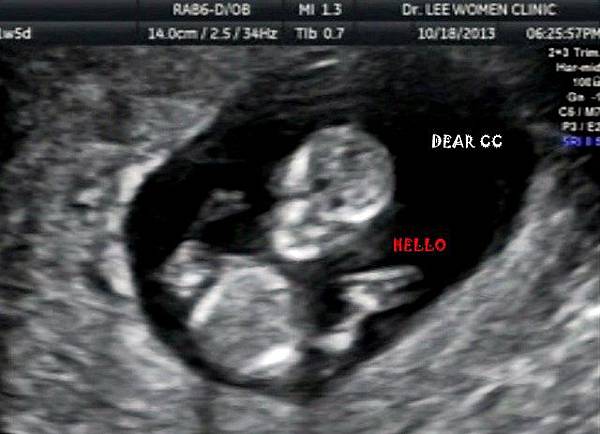

懷孕約11w是我們排定做初唐的日子

醫生是同診所的王翰洲醫師,他似乎是婦幼的退休醫生

大致來說,初唐就是要檢查胎兒的頸部透明帶

可以從頸部透明帶的厚薄(越薄越好)加上媽媽的抽血推測得唐氏症的機率

做頸部透明帶的時間大約半小時

王醫師很親切,邊照邊跟我們解釋(大推王醫師)

蕭CC的鼻骨好挺,然後下巴很漂亮

蕭CC也很配合,在照頸部透明帶的時候,有乖乖躺好

讓醫生量了好幾次,取平均值,1.2mm

根據醫生解釋,是低風險

照著照著,蕭CC突然坐起來向我們揮手打招呼,然後再躺回去

本來我照到快睡著,這舉動笑翻大家,也太可愛了